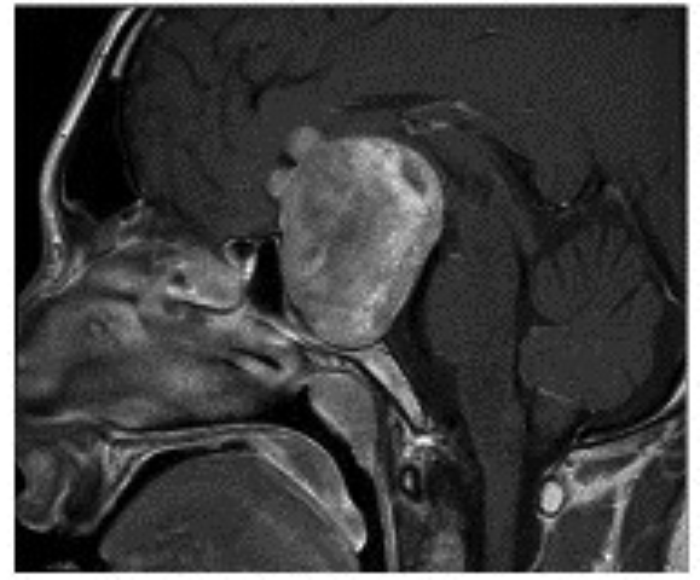

A 26-year-old primary school teacher with 10 diopters of myopia was referred to the laser centre for evaluation prior to possible treatment. He had been seen since his school days by a number of different optometrists because of his high myopia and appropriate spectacles were prescribed and later contact lenses. In the laser centre he was noted to have a significant degree of exo deviation (exophoria / exotropia) so the opinion of a motility specialist was arranged, who advised surgical treatment. On further questioning he admitted to having intermittent headache and even though the optic discs were considered to be normal for his degree of myopia fortunately a brain scan was advised prior to the proposed surgery. The result of MRI scan is shown in Figure 5.

Figure 5: MRI scans of the 26-year-old myopic patient showing a large pituitary tumour.

Top = Axial image. Middle = coronal image. Bottom = saggital image.

In the neuro-ophthalmology clinic he again denied any subjective visual problems apart from those associated with his high myopia. His acuity was confirmed as 6/6 N5 in each eye with normal colour vision, and the optic discs again could have been considered within normal limits for his degree of myopia. Now at last at this, his 16th eye examination, a confrontation visual field was performed and a complete bitemporal hemianopia easily elicited. Formal visual fields confirmed the bitemporal hemianopia with contraction of the residual nasal fields (Figure 6). His prolactin level was normal so he was referred urgently to neurosurgery. His trans-sphenoidal hypopysectomy extended to over three hours as a solid type tumour was encountered which was not possible to remove completely. At follow-up there was no improvement in his visual field defect but, as expected post-operation, the optic discs were now pathologically pale. He is on replacement hormonal treatment and requires long-term follow-up in endocrine, neurosurgical and neuro-ophthalmology clinics.